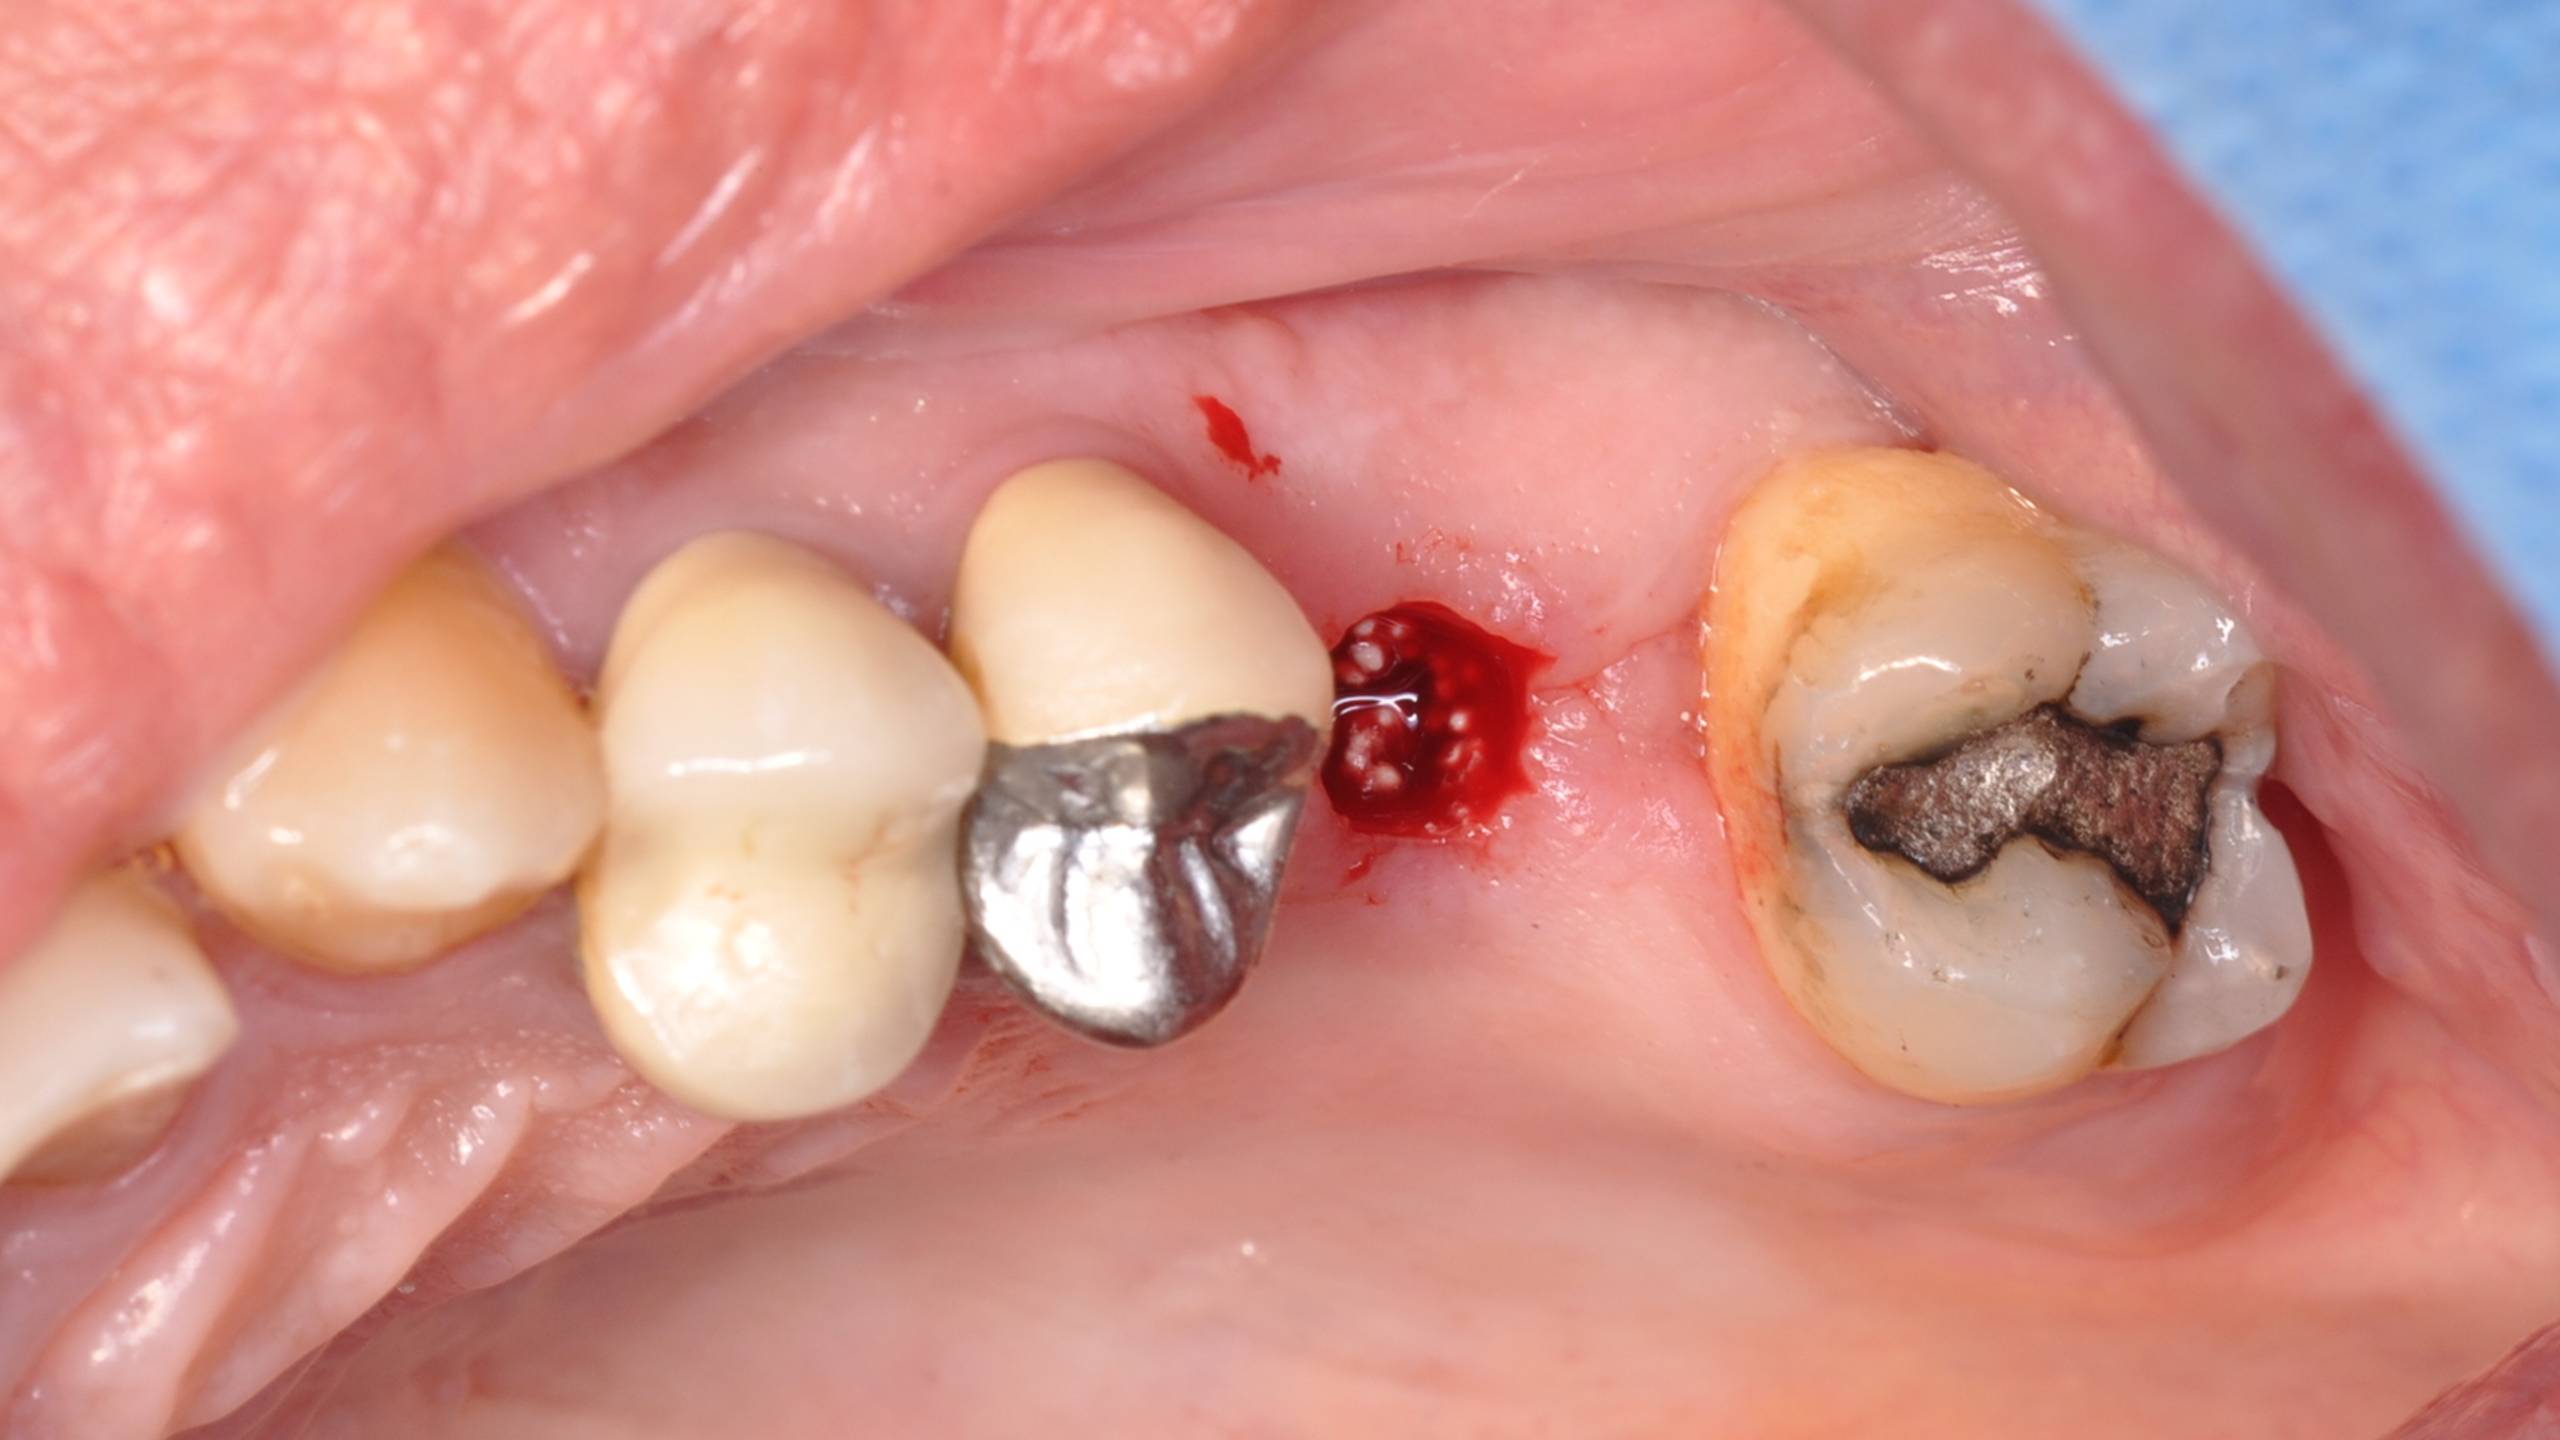

Cas d’une patiente présentant une absence de 26.

Réalisation d’une gingivectomie permettant un abord crestal dans le but de la pose d’un implant en flapless.

Utilisation d’un osteotome afin de fracturer le plancher sinusien, puis apport d’un matériau de comblement synthétique ( Easygraft SUNSTAR) per opératoire.

Visualisation du matériau avant qu’il ne soit refoulé dans le sinus.